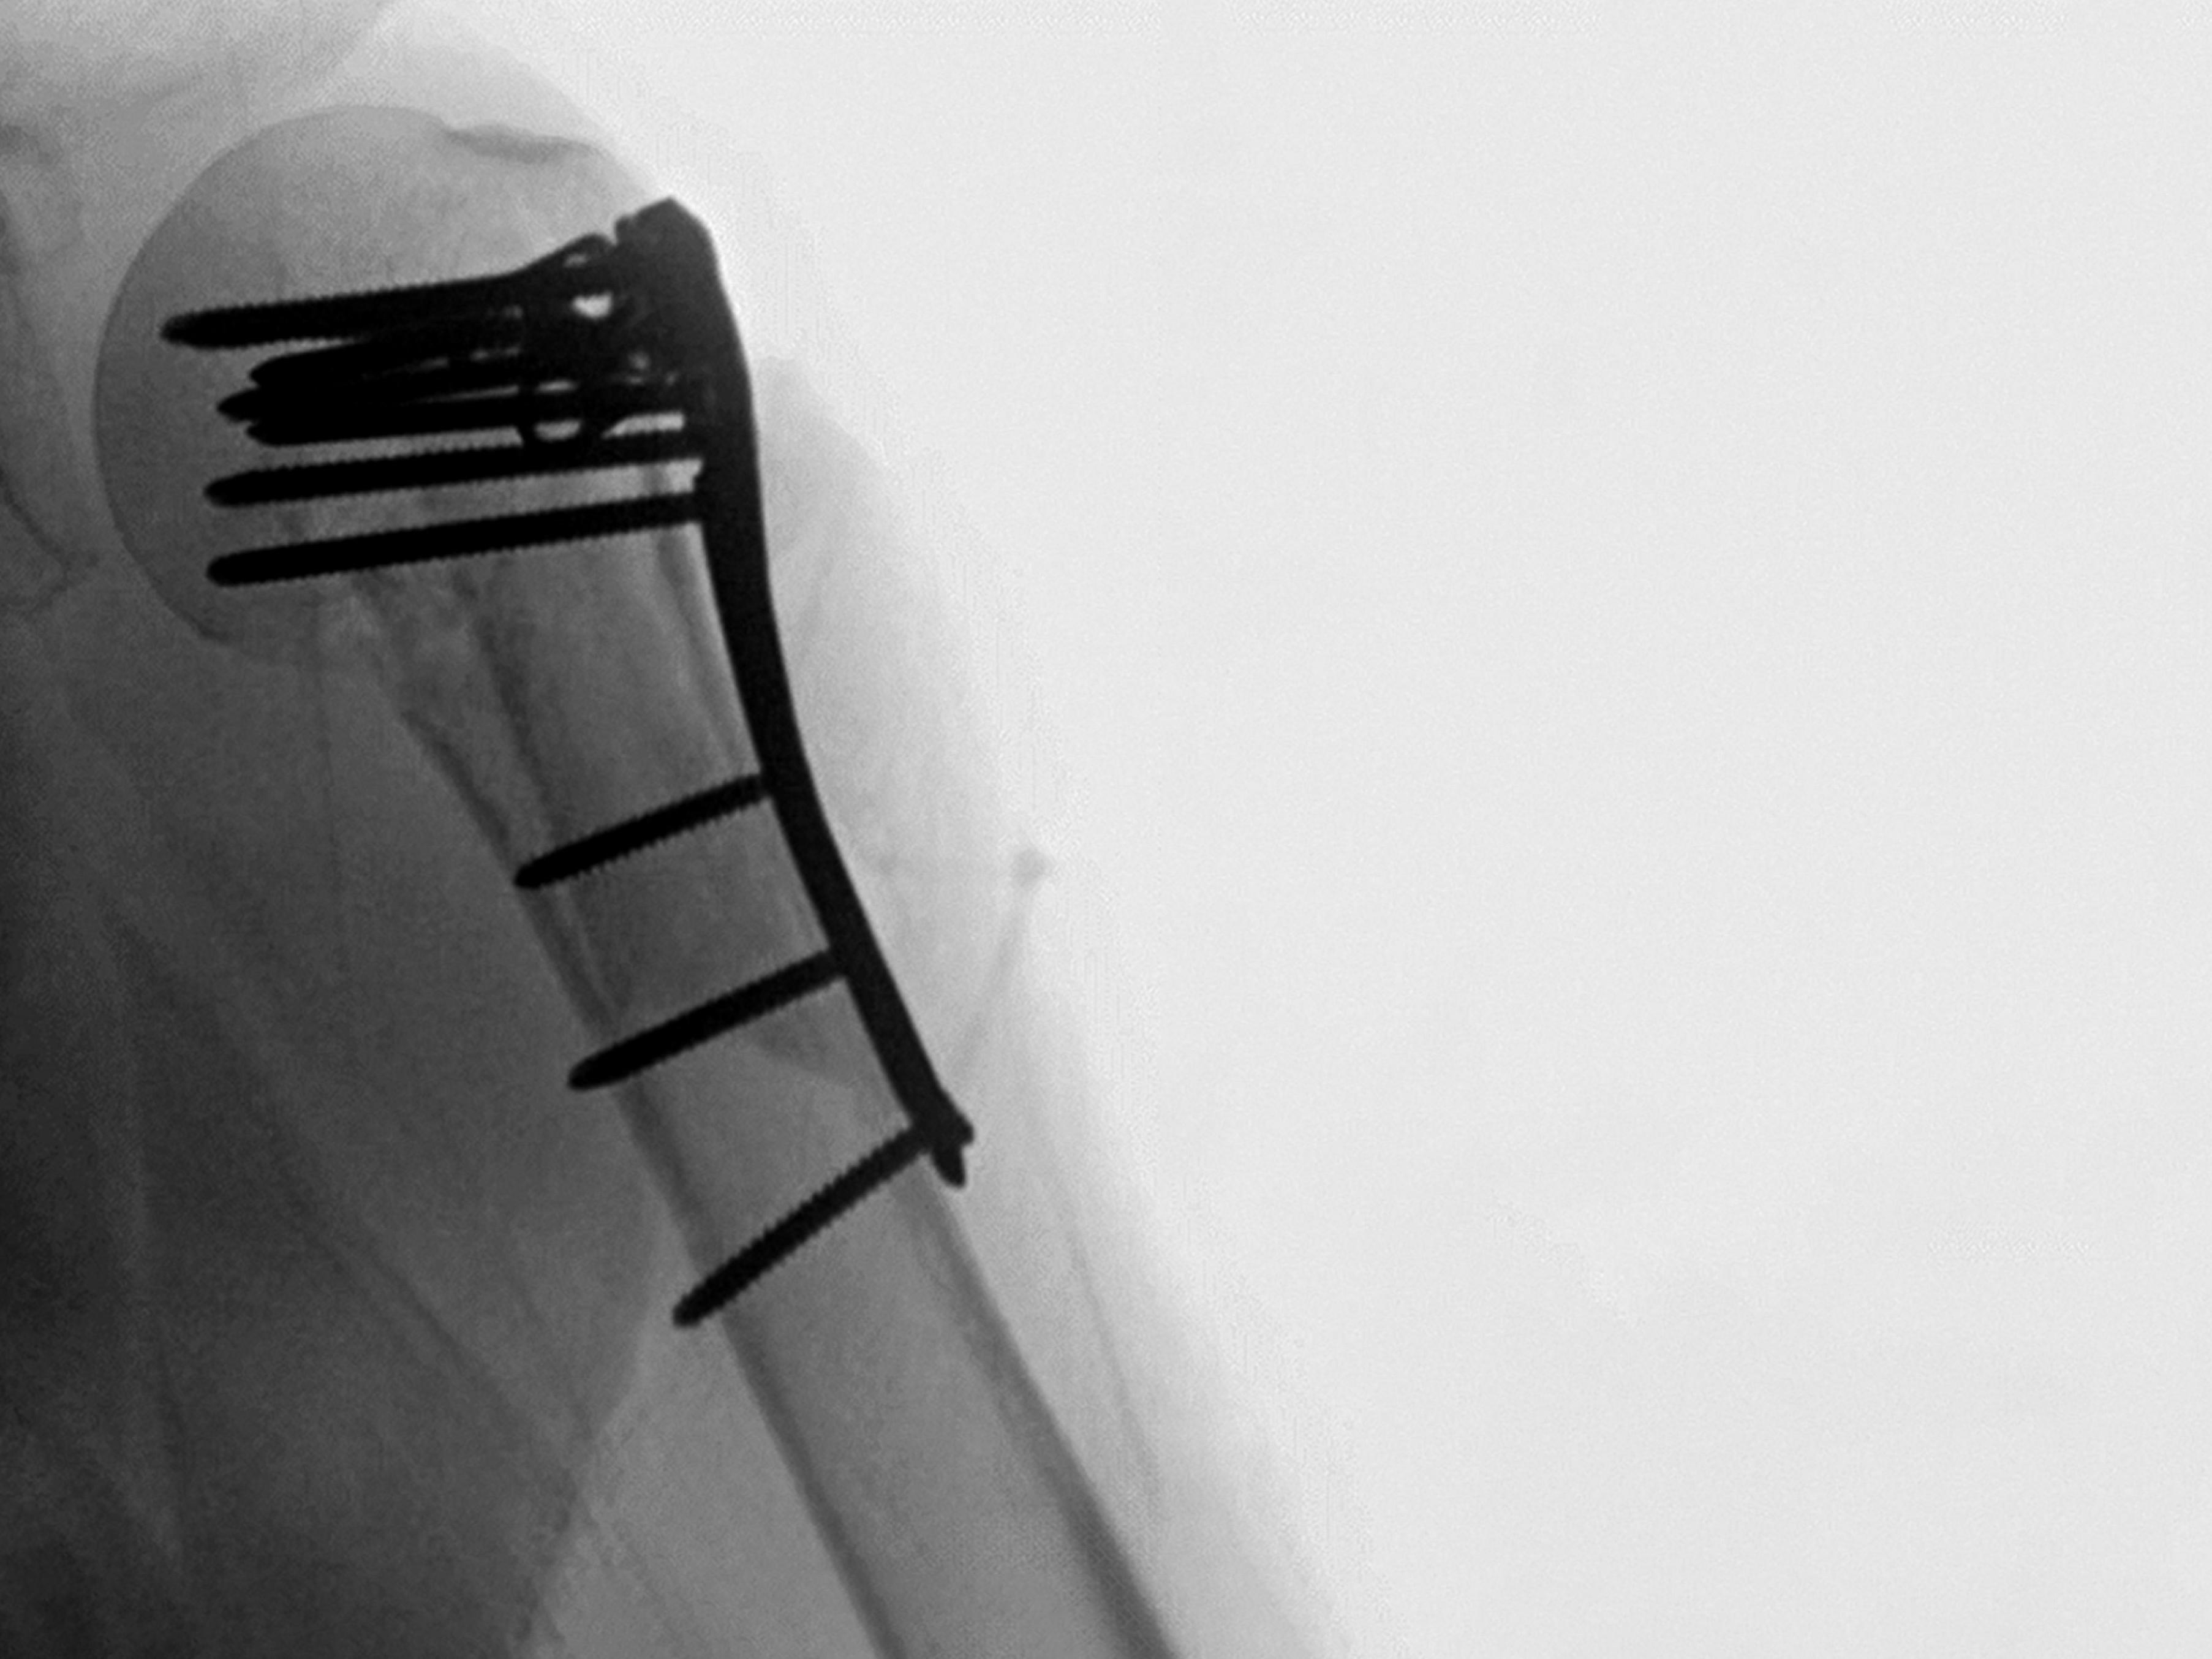

TAMINA CLINICAL CASE: FIBULAR STRUT GRAFT AUGMENTATION OF A PROXIMAL HUMERUS FRACTURE

We present a case of a 3-part proximal humerus fracture with varus, apex anterior angulation and anterior translation of the humerus. A fibular strut was used to augment the bone.

TAMINA fibular strut augmentation